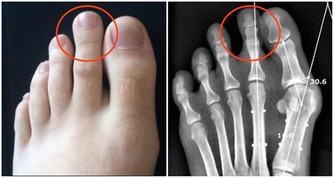

據臨床觀察,白血病患者的常見症狀包括體重異常減輕、疲倦乏力、呼吸急促、淋巴結腫大、胃部腫脹、發熱盜汗、骨痛或關節痛、頻繁反复地感染等。而患者也會感到皮膚組織瘙癢難忍,或是非常容易造成淤青或出血。如果發現自己的皮膚有類似的情況出現,一定要立即檢查,因為許多人都會忽視自己皮膚上的小問題。